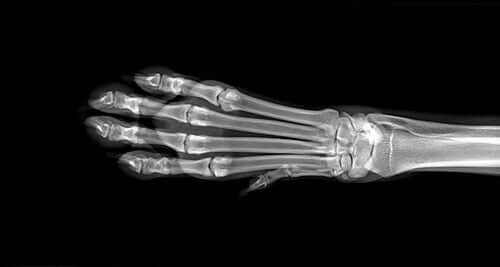

Para determinar a causa do inchaço, o veterinário irá fazer uma série de exames de diagnóstico, entre os quais se destacam a análise de sangue e urina, bem como raios-X dos membros. Caso estes últimos sejam inconclusivos, pode ser necessária uma ressonância magnética. Se houver suspeita de osteossarcoma, será realizada uma biópsia óssea.